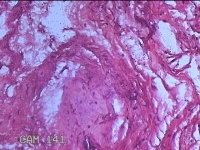

右侧髋部结节

性别

女

年龄

50岁

临床诊断

皮下结节

一般病史

发现右髋部结节1个月余。

标本名称

大体所见

灰白粉红色结节1.3x0.5x0.2cm一个,表面光滑,切开结节呈实性,切面灰白粉红色,质软。

有的地方感觉像个血管瘤,未见明确恶性